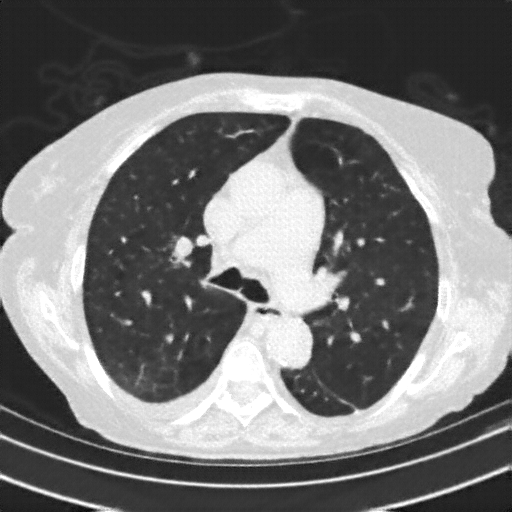

Targeted Slice 70 - HU-Space Analysis (Generated vs Real Venous)

0.762

HU SSIM

169.4

HU RMSE

78.9

HU MAE

Average HU-Space Metrics Across All Slices (153 slices) - Generated vs Real Venous

0.753

HU SSIM (Avg)

155.9

HU RMSE (Avg)

73.8

HU MAE (Avg)

Generated VENOUS CT scan (A→B translation)

Full window (WL 1023.5, WW 4095 β†’ Low βˆ’1024, High +3071)

Actual HU range: [-1024.0, 1137.2]